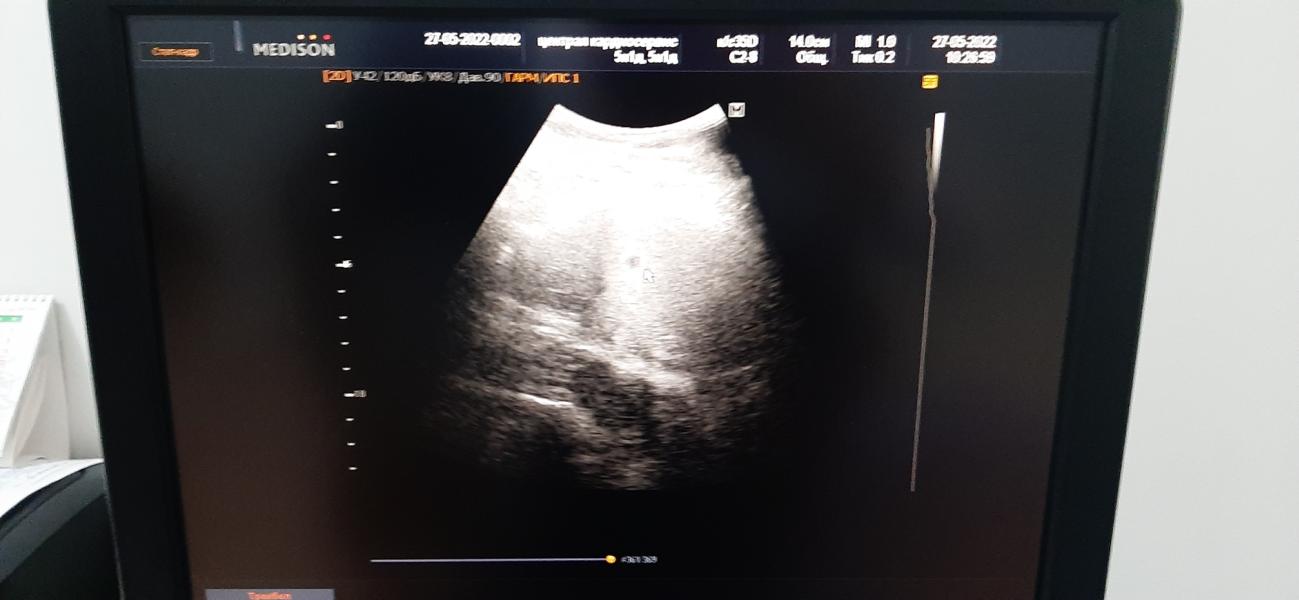

Всем приветик 🥰 помните я говорила что у меня мультифоликцлярность, ну вот, а отучила дочку от груди, и в том же месяце забеременела🤗🤗🤗 сейчас нам 16 недель, продолжение расскажу в след записе .....